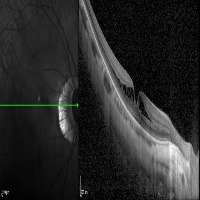

Medical Imaging Analysis: The "three-segment" model can be used by healthcare professionals for enhanced analysis of medical imaging, such as MRI or CT scans. It will help in identifying cleave classes, which can improve detection and diagnosis of potential issues in the brain, particularly those related to retina or neural connections.

Retinal Disease Diagnosis: Ophthalmologists could utilize the model to get help in diagnosing retinal diseases. It can help to identify any abnormalities by differentiating between the 'out', 'in', and 'retina' segments, enabling early detection of conditions such as retinal detachments or macular degeneration.

AI in Surgery: The model can be used to assist surgeons during complex neuro or eye surgeries. It can provide enhanced visualization, enabling real-time differentiation between various segments, leading to more precision in surgical procedures.

Medical Training and Education: The model can be used in medical learning settings, providing students with valuable visual learning material. It could serve as an advanced tool for the understanding of the retina and other segments of the brain or eye.